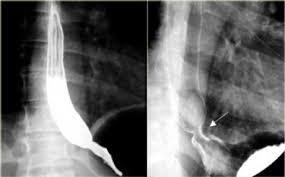

위내시경검사를 통해 위식도 접합부 염증여부를 확인하고 위식도 역류에 의한 식도 점막 손상이 있는지를 확인하고 역류성식도염을 진단할 수 있다고 한다.

위내시경검사는 특수 카메라가 달린 내시경을 입을 통해 삽입한 후 식도부터 위까지 실시간으로 모니터를 보면서 병변 유무를 확인할 수 있다고 한다. 위내시경검사를 통해 역류성식도염 뿐 아니라 식도암, 위염, 위암 등의 질환을 진단할 수 있다고 한다.